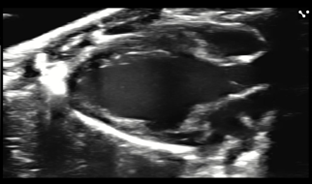

Custom services Ophthalmology

Using high-resolution ultrasound, we monitor eye development from embryonic stages through adulthood in rodent models. Our services include:

- Volumetric measurements of ocular structures for growth and morphology studies.

- Vascular assessment using Doppler imaging to evaluate ocular blood supply, including the central retinal artery.

- Blood flow analysis with PW Doppler for functional insights.

- Intraocular image-guided injections (IGI) for targeted delivery of compounds or contrast agents.

This approach supports research in developmental biology, ophthalmic diseases, and therapeutic interventions.